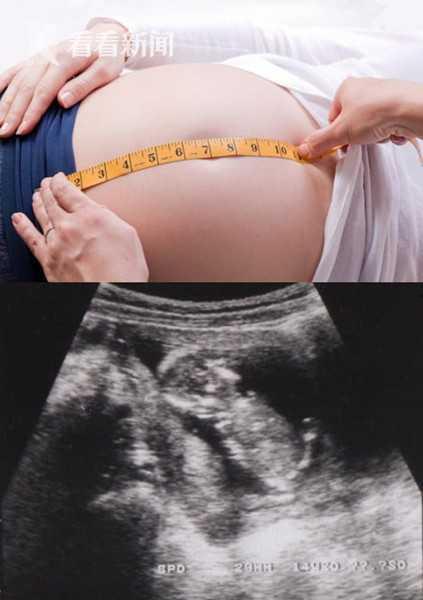

在日本,孕妇产前准备可是件大事。从怀孕初期开始,孕妇就会接受全面的产检,医生会根据孕妇的体质和胎儿的发育情况,制定个性化的产前护理方案。